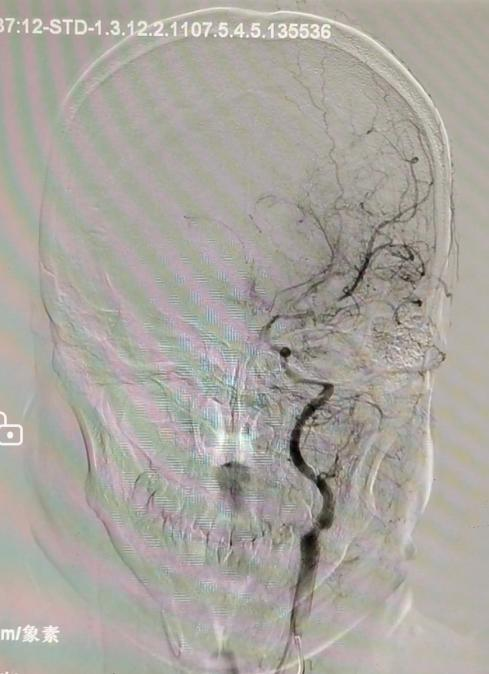

硬脑膜动静脉瘘患者同样在个性化方案中重获新生。患者因反复头晕,在外院怀疑静脉畸形,来到东方总院后,脑血管造影明确为硬脑膜动静脉瘘。通过详细的沟通,家属选择介入栓塞,吴全主任团队采用介入打胶栓塞的治疗方式,精准地堵住异常血管,一次性完全栓塞,术后患者头晕症状消失,生活质量大幅提升。

颈内动脉剥脱患者的经历,便是个性化治疗的有力见证。这位患者辗转多家医院,被诊断为颈内动脉狭窄,来到淮南东方总院。神经外科医疗中心张德辉院长团队深知手术风险与难度,先为其进行脑血管造影,精准掌握血管病变情况。随后,在全麻下为患者施行颈内动脉剥脱术。手术过程中,医生凭借高超技艺,小心翼翼地操作,避开周围复杂的神经和血管,将颈内动脉斑块完全剥离,术后颈内动脉血流再通良好。